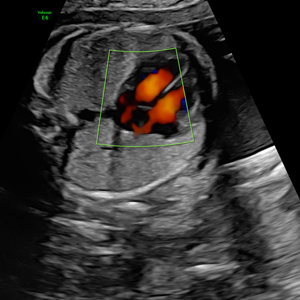

Dr. Homero Flores Tamez

Ginecología y Obstetricia

Medicina Materno Fetal

- Instituto Nacional de Perinatología

- Pionero en México en ofrecer diagnóstico por ultrasonido dentro del consultorio, así como en incorporar tecnología 3D y Doppler.